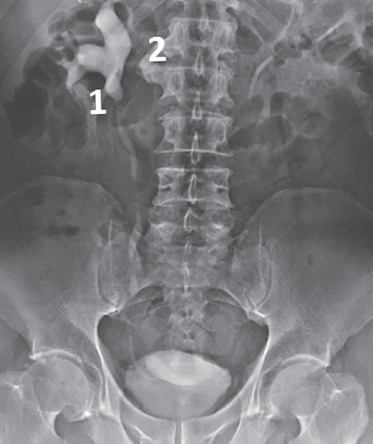

Пациент К., 68 лет, в мае 2017 г. поступил по срочным показаниям в кардиологическое отделение ПГКБ им. Е.Е. Волосевич с жалобами на нехватку воздуха, общую слабость. В анамнезе острый инфаркт миокарда, стентирование коронарных артерий в 2013 г. Получает консервативное лечение по поводу доброкачественной гиперплазии предстательной железы. При обследовании выявлены гиперкалиемия (6,4 ммоль/л), гиперкреатининемия (267 мкмоль/л), повышение мочевины крови до 18 ммоль/л. При УЗИ почек обнаружена двусторонняя выраженная пиелоэктазия. Пациент консультирован урологом — диагностирована доброкачественная гиперплазия предстательной железы, осложненная двусторонним гидроуретеронефрозом. Выполнена двусторонняя пункционная нефростомия. При контрастировании ультравистом выявлено выраженное расширение чашечно-лоханочных систем и верхних отделов мочеточников с двух сторон. Заподозрены стриктуры обоих мочеточников. Пациент обследован в урологическом отделении ПГКБ в марте 2018 г. При цистоскопии патологии не выявлено. Произведена двусторонняя уретероскопия до уровня стриктур, выполнена биопсия из участков, подозрительных на опухоль. Гистологическое заключение не подтвердило наличия опухоли. При цитологическом исследовании мочи атипичные клетки не обнаружены. Пациент консультирован онкоурологом — данных за онкозаболевание на момент осмотра не получено. Оперативное лечение по поводу стриктур мочеточников было отложено до января 2019 г. из-за обострений хронического пиелонефрита. 17 января 2019 г. накануне операции произведена двусторонняя антеградная пиелоуретерография, которая показала наличие справа в нижней трети мочеточника мягкотканного образования размером 2 × 2 см, обтекаемого контрастом (симптом «змеиного жала») (рис. 5).

На антеградной пиелоуретерограмме слева мочеточник контрастируется только до уровня L4 (рис. 6). Предварительный диагноз: «Рак обоих мочеточников».

Рис. 6. Пациент К., 68 лет. Антеградная пиелоуретерография слева. Стрелкой отмечена локализация опухоли мочеточника

Fig. 6. Patient K., age 68. Antegrade pyeloureterography left. The localization of the ureteral tumor is marked by arrow